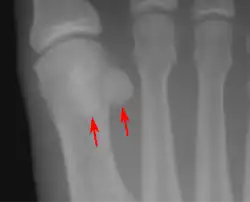

Lateral view.[11]

Bipartite medial sesamoid bone under the first metatarsophalangeal joint of the great toe of the left foot of an adult woman.

- One or both of the sesamoid bones under the first metatarsophalangeal joint (of the great toe) can be multipartite – in two or three parts (mostly bipartite – in two parts).[12]